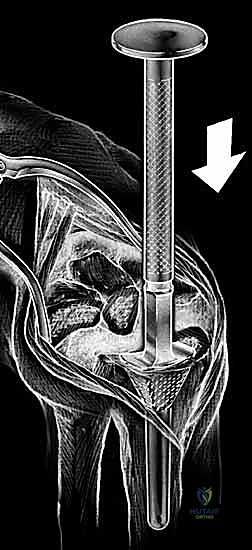

With the extensor tendons mobilized and safely retracted, a longitudinally based capsulotomy is performed. The capsule is reflected as radially and ulnarly based full-thickness flaps, exposing the distal radius and the entire carpus down to the base of the third metacarpal. Preparation of the distal radius involves scoring a reference line to ensure the DRUJ is preserved. The radial canal is sequentially broached to accept the modular radial stem. The modular radial stem component is designed to fill the distal radius canal to prevent loosening and provide rotational stability. While approved for implantation with bone cement (PMMA), most modern wrists are implanted with press-fit, cementless fixation to encourage osteointegration. Cement is generally reserved for cases of significantly compromised bone stock, severe osteopenia, or revision scenarios.

Following capitate reaming, the chosen carpal plate and stem are assembled and inserted into the capitate and seated onto the resected carpal surface. The carpal plate is anchored to the carpus with a radial screw that optimally does not penetrate the second metacarpal, and a second screw placed ulnarly into the hamate. This construct ensures stable distal fixation while avoiding the deleterious lever arm of a long metacarpal stem. Trial reductions are performed to assess stability, range of motion, and impingement. Once kinematics are confirmed, the definitive ultra-high-molecular-weight polyethylene (UHMWPE) body—which is direct compression molded onto a cobalt chrome alloy radial body—is impacted. The capsule and extensor retinaculum are meticulously repaired to prevent extensor tendon bowstringing and provide a robust soft tissue envelope over the implant.